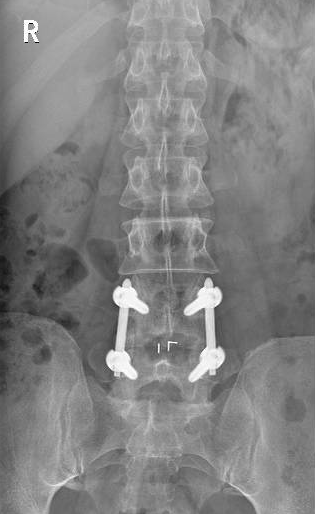

50歲的游先生因長期勞損,飽受腰痛與下肢放射痛折磨,保守治療無效,又因顧慮傳統(tǒng)手術創(chuàng)傷大、需植入螺釘而遲遲未決。我院脊柱團隊為其施行UBE下單側(cè)入路雙側(cè)減壓+椎間盤摘除+神經(jīng)根松解術,手術僅耗時50分鐘,術后24小時即可下床,3天出院,1個月后順利重返工作崗位。 內(nèi)鏡下減壓后影像 術后切口 病例二:高齡多病患者的“安全之選” 76歲的徐老先生患有嚴重腰椎管狹窄伴滑脫,合并高血壓、糖尿病,手術風險極高。經(jīng)多學科協(xié)作,團隊采用UBE技術為其完成減壓、復位、融合與內(nèi)固定,術中出血僅30毫升,無并發(fā)癥發(fā)生。術后第3天,老人已能下地行走,一周出院,家屬特贈錦旗致謝。 內(nèi)鏡下置入融合器 術后切口 術后DR片見滑脫已復位 病例三:復雜結(jié)核感染患者的“精準施治” 72歲的劉奶奶曾因椎體骨折接受骨水泥手術,后確診腰椎結(jié)核伴椎管內(nèi)膿腫,且體質(zhì)虛弱、伴有低氧血癥與貧血。團隊果斷采用UBE行椎管減壓+膿腫清除+骨水泥取出術,以微小切口解決重大隱患,術后患者疼痛顯著緩解,恢復良好。 術中取出椎管內(nèi)干酪樣膿腫 術中取出的骨水泥